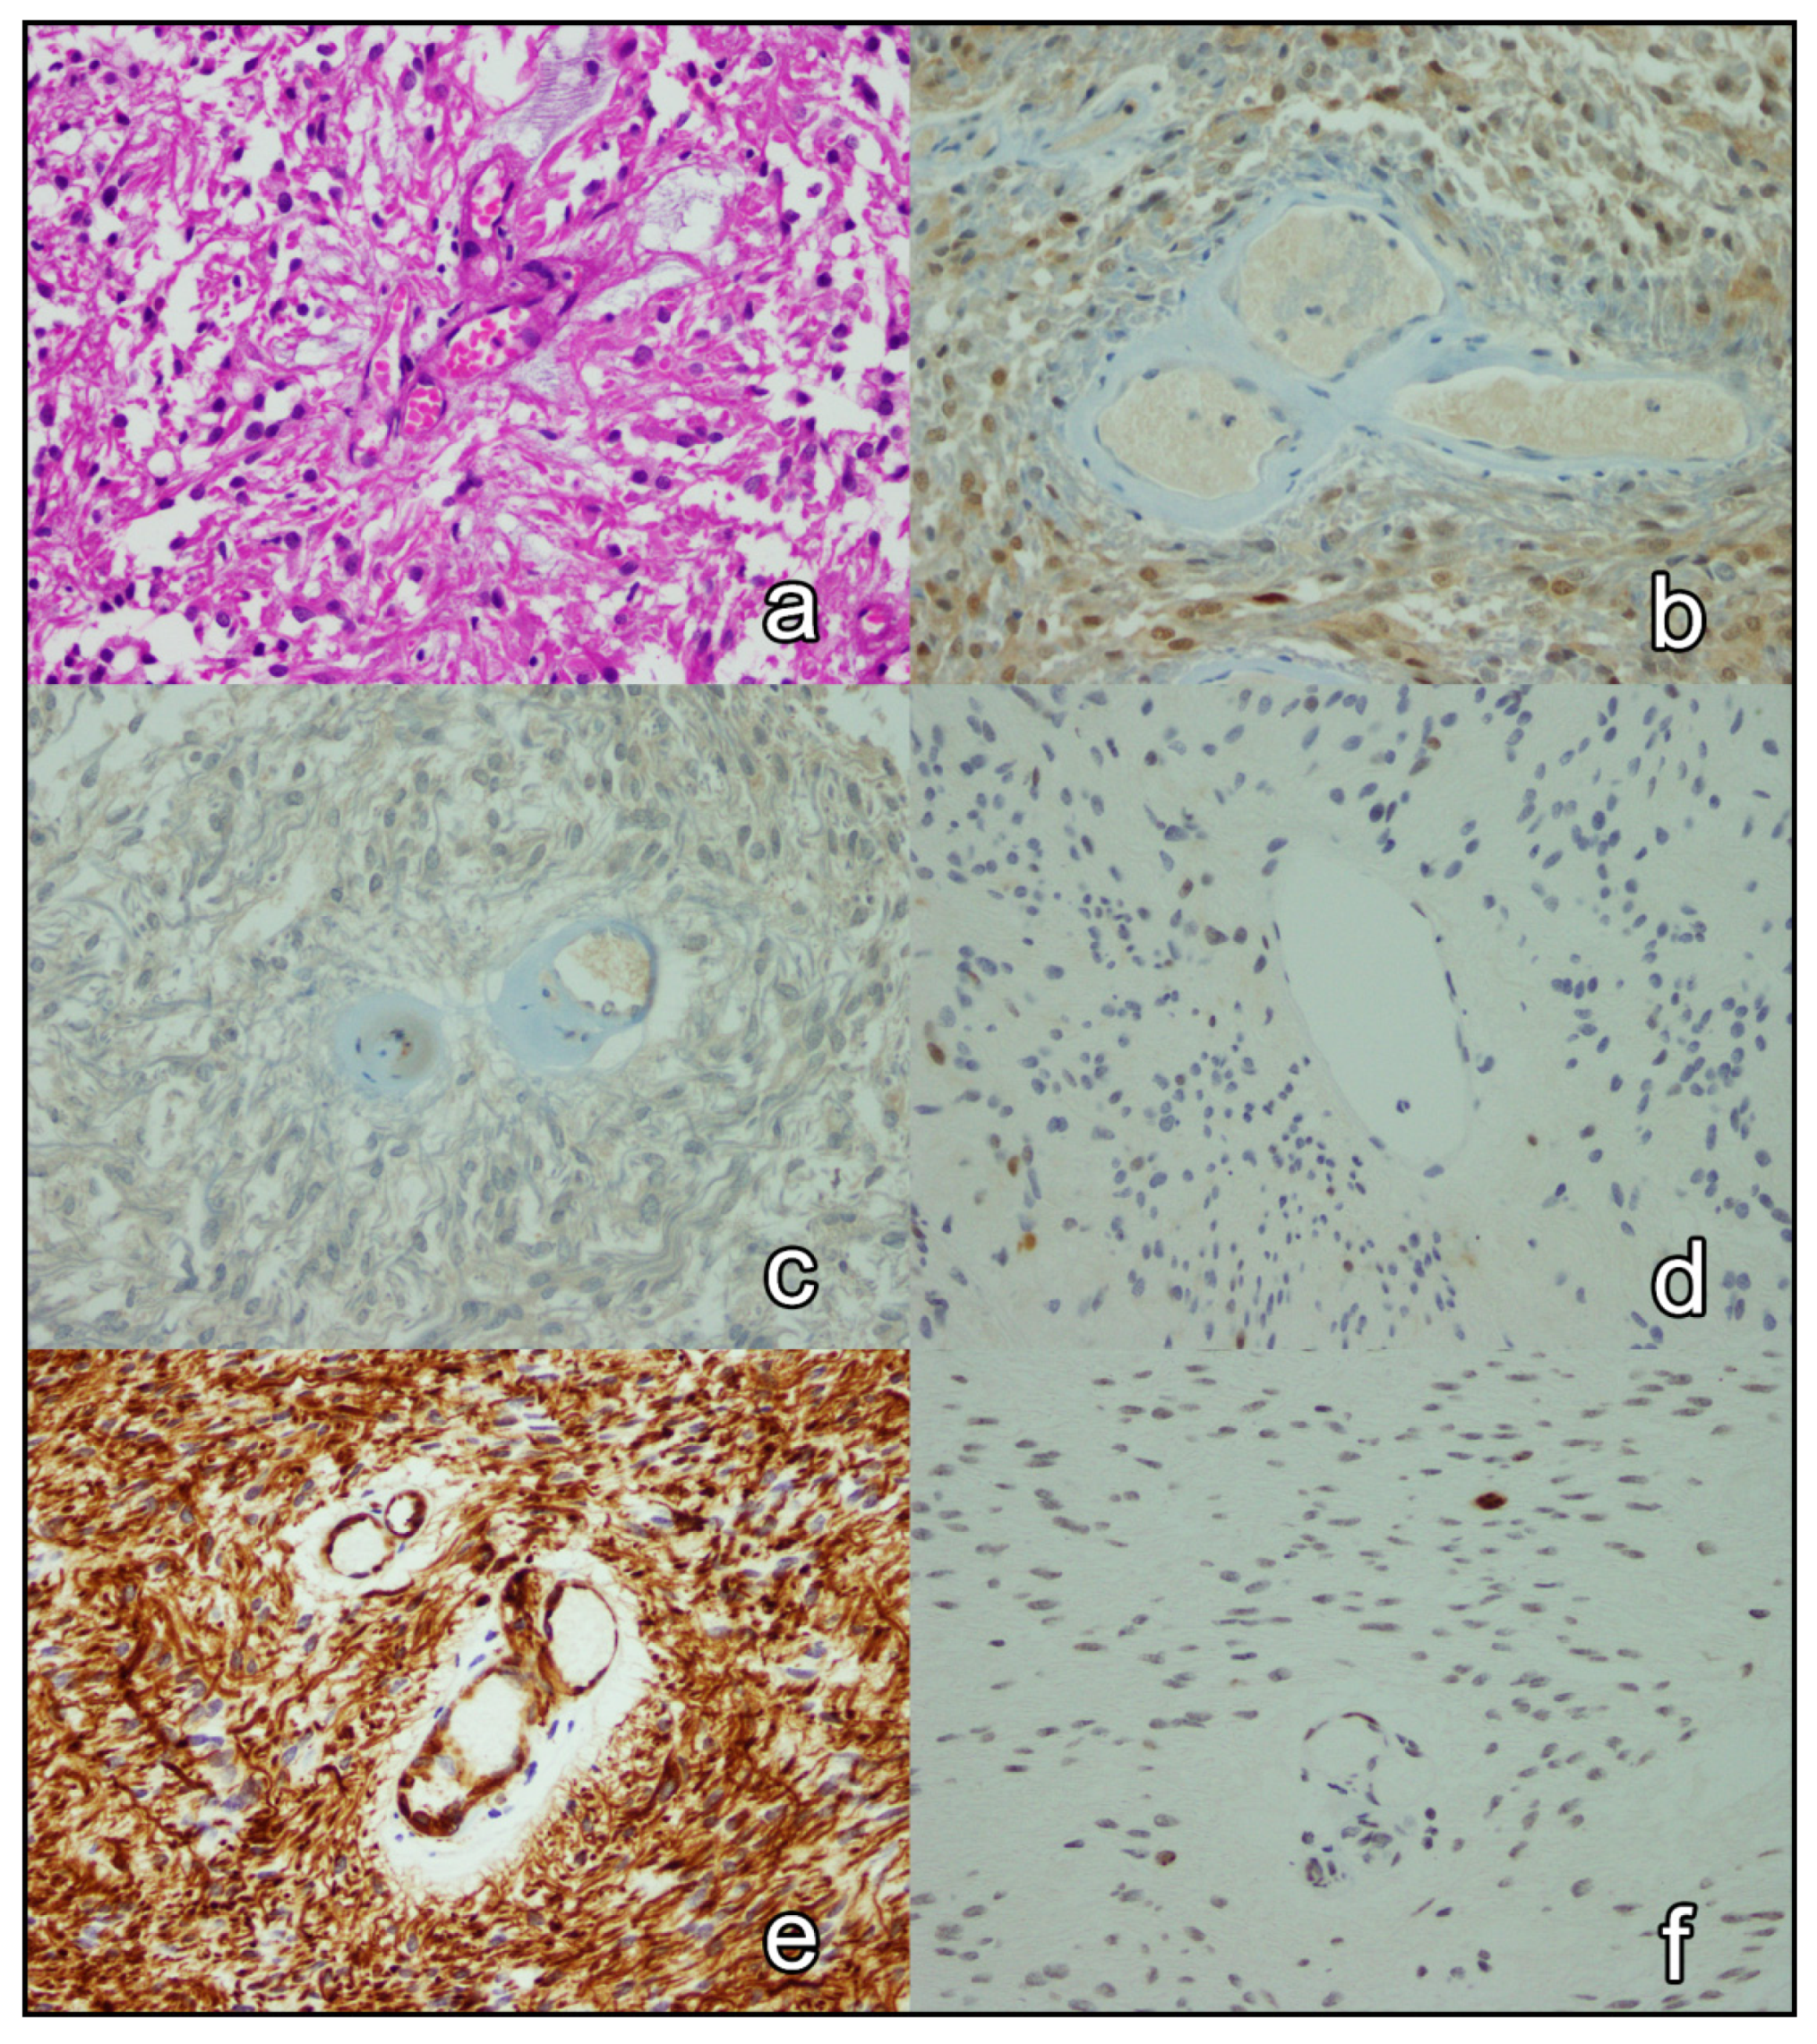

3.3. Immunohistochemical Analysis